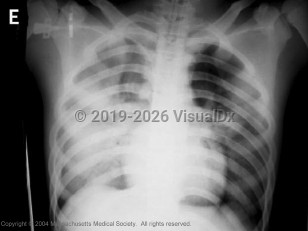

Traditionally, the incubation period is generally between 2-5 days, but an upper limit of 8 days is possible. Most patients have headache, malaise, high fever, sore throat, cough, shortness of breath, and myalgia. Conjunctivitis, watery diarrhea, abdominal pain, vomiting, pleuritic pain, and bleeding from the nose have also been reported. Respiratory distress, tachypnea, and inspiratory crackles are present on physical examination. Lymphopenia and thrombocytopenia are commonly present. The frequency of milder illnesses, subclinical infections, and atypical presentations such as encephalopathy is not known. Pregnant individuals are at increased risk for severe illness from influenza.

Atypical presentations of avian influenza have been reported. Patients have developed nausea, vomiting, and diarrhea preceding acute respiratory failure. Progression to acute respiratory distress syndrome (ARDS) and respiratory failure is common. Complications have included bacterial sepsis, pulmonary hemorrhage, and multi-organ failure. The mortality rate of hospitalized patients has been high due to progressive respiratory failure.